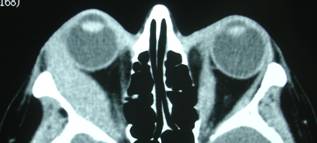

| CT scan evidencing intraconically growing hemangioma | |

They can appear anywhere: from the bone tissue itself to orbital tissues localized in the lacrimal gland, anterior orbit or eyeball. They can be found just behind the eyeball (intraconical) or outside the muscles (extraconical).

Depending on location they will behave in a more or less aggressive manner affecting the eye.